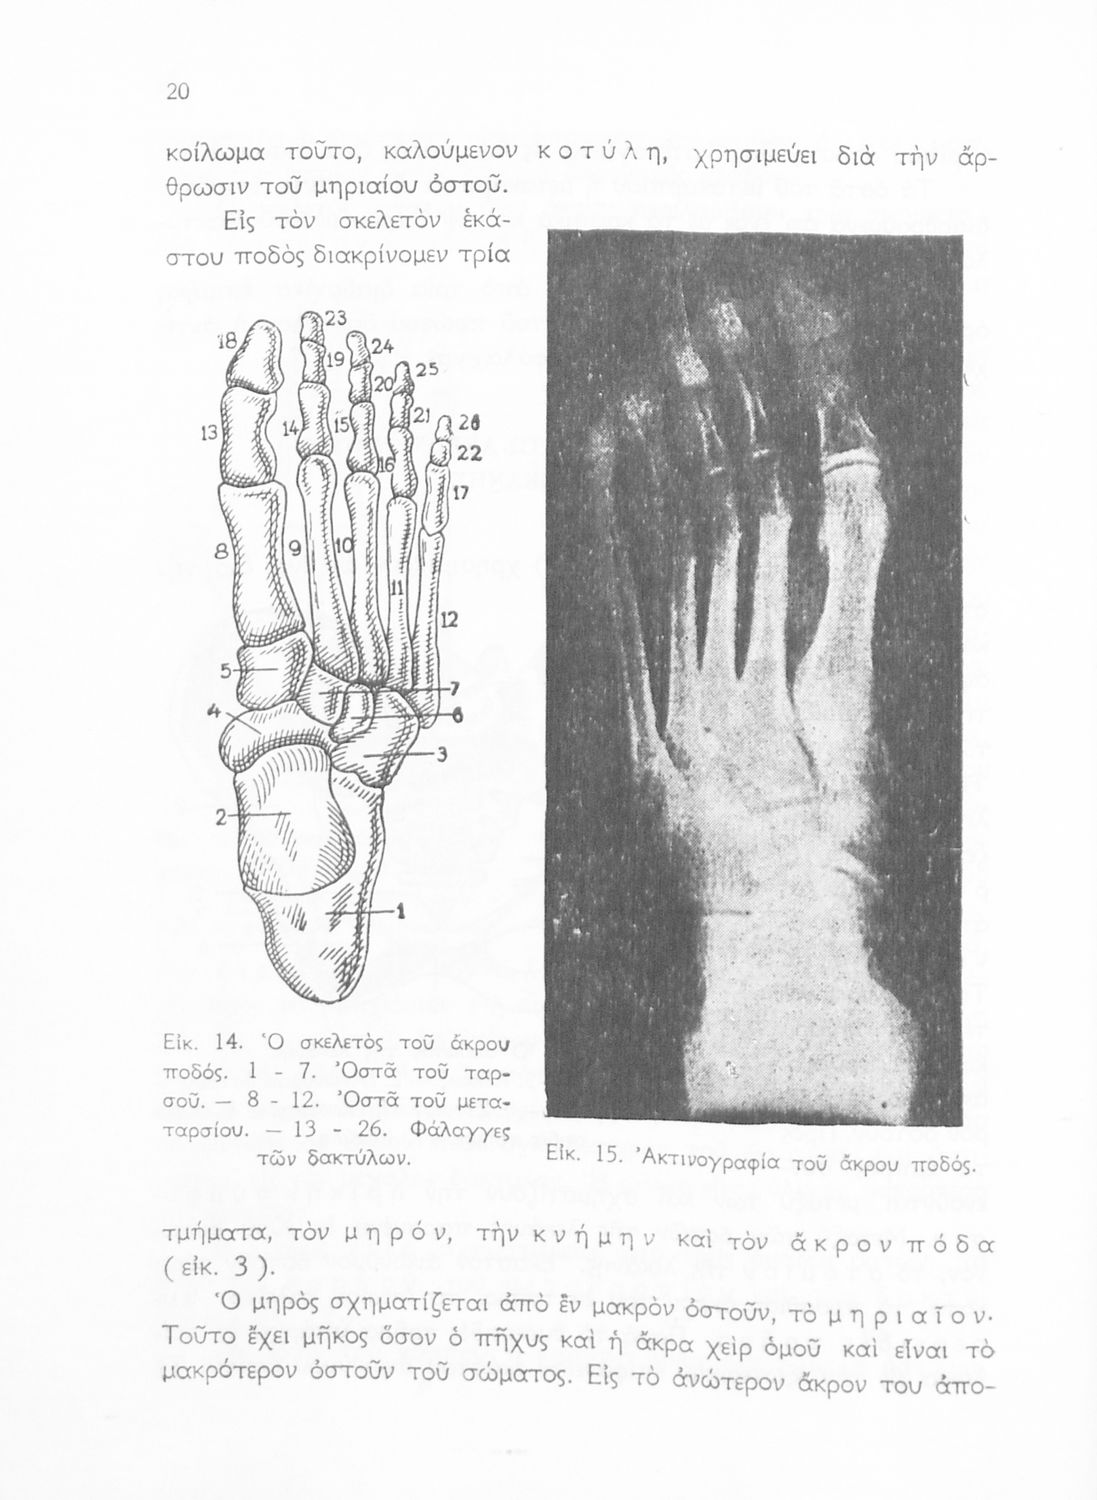

Σελίδα #020